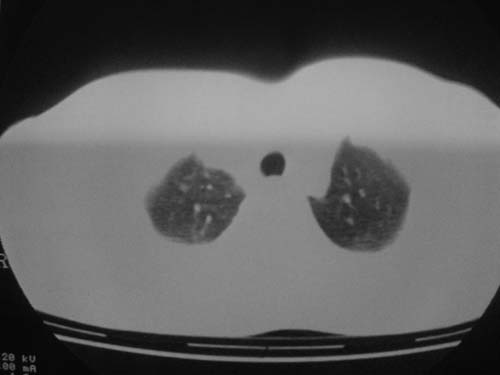

这是第三天拍的片子.